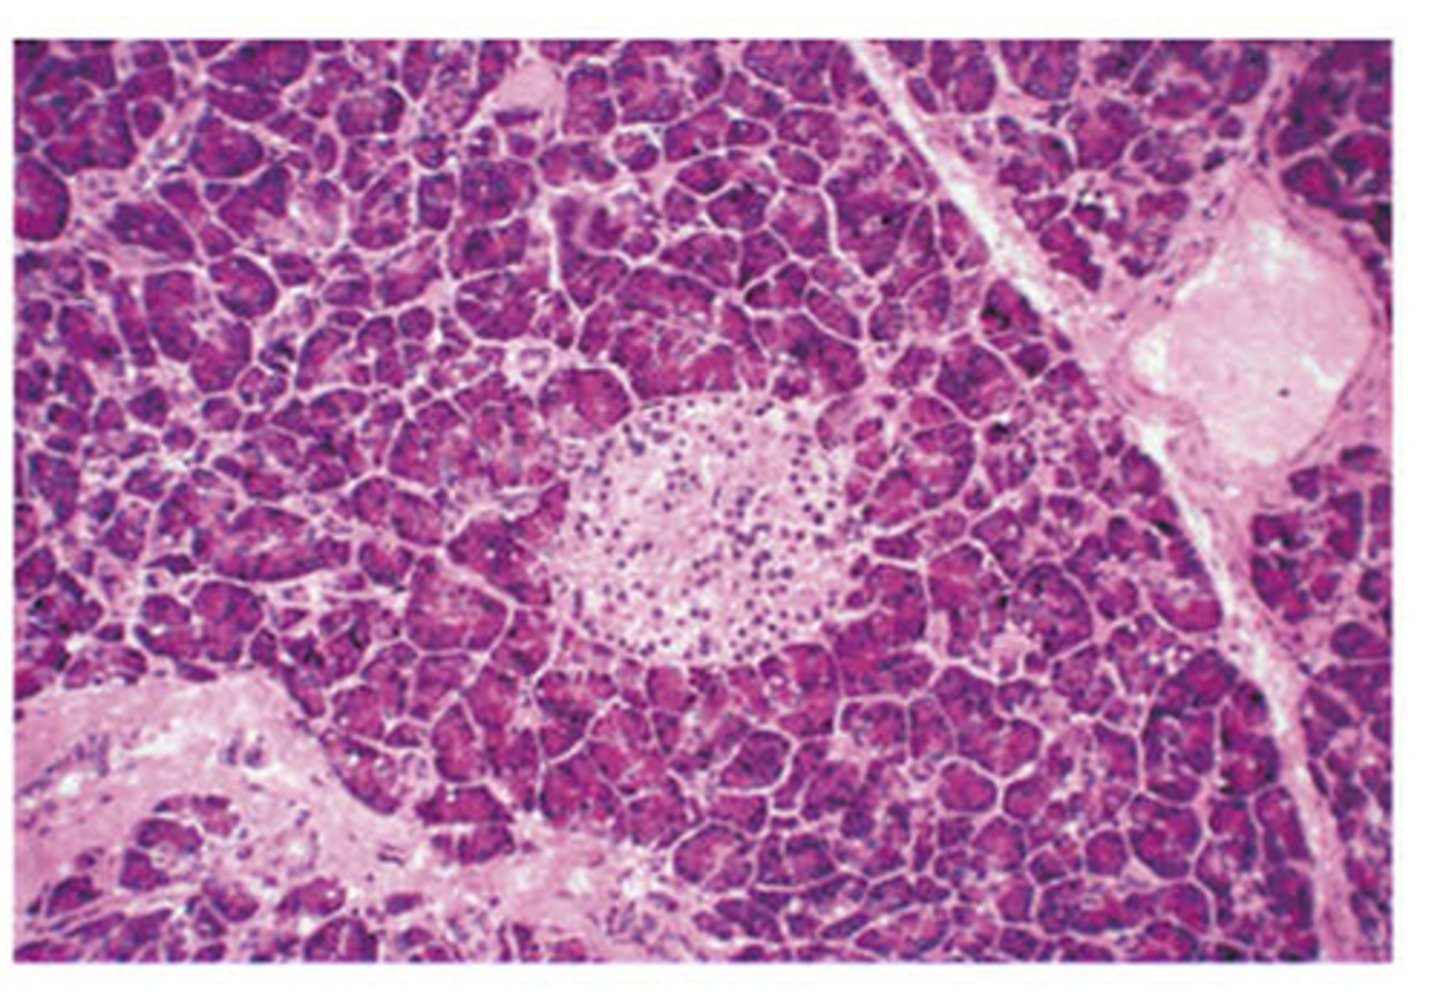

Pancreas cells cross section

Consists of exocrine cells and endocrine cells

Endocrine cells islet of langerhans of the pancreas

Secretes: insulin, glucagon, somatostatin

Exocrine Tissue of pancreas

A

Synthesizes and secretes digestive proenzymes and enzymes